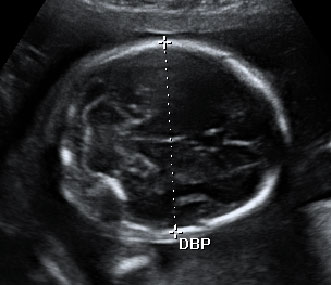

Las ecografías en 4D realizadas en la semana 20 de embarazo permiten ver el sexo femenino del feto con nitidez. En este caso, se ha capturado la imagen de los genitales femeninos, en concreto, la vulva.

En este ultrasonido, podemos ver la vulva del feto y otros pequeños detalles del sexo fetal.